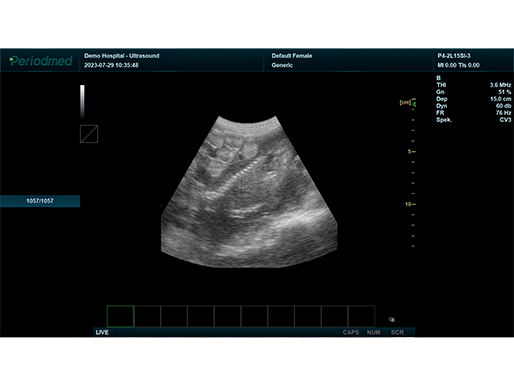

B模式 腹部 羊

凸阵探头-B模式-腹部 羊